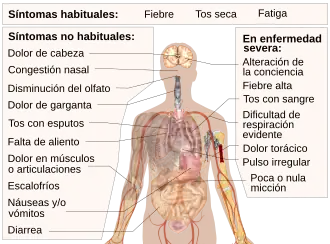

Signos y síntomas

Las personas infectadas pueden estar asintomáticas o presentar un cortejo de síntomas que oscilan desde leves a muy graves, entre ellos fiebre, disnea[104][105][106] y tos seca.[13] La COVID-19 afecta de distintas maneras en función de cada persona. La mayoría de las personas que se contagian presentan síntomas de intensidad leve o moderada, y se recuperan sin necesidad de hospitalización. La diarrea y otros síntomas de rinofaringe, como estornudos, rinorrea y dolor de garganta, son menos frecuentes.[107] Aunque las personas de avanzada edad son más vulnerables a la enfermedad, a mitad de marzo de 2020, la OMS recordó que los jóvenes también pueden tener complicaciones e incluso llegar a la muerte por el virus.[108]

Los síntomas de la COVID-19 son inespecíficos y su presentación, según la OMS, puede incluso carecer de síntomas (asintomático). En base a una muestra estadística de 55 924 casos confirmados por laboratorio, la frecuencia de presentación de los síntomas en la población china era la del cuadro adjunto.[1]

| Síntoma presente: | |

|---|---|

| Fiebre | 87,9 |

| Tos seca | 67,7 |

| Fatiga | 38,1 |

| Producción de esputo | 33,4 |

| Disnea (dificultad respiratoria) | 18,6 |

| Dolor muscular o dolor en las articulaciones | 14,8 |

| Dolor de garganta | 13,9 |

| Dolor de cabeza | 13,6 |

| Escalofríos | 11,4 |

| Náuseas o vómitos | 5,0 |

| Congestión nasal | 4,8 |

| Diarrea | 3,7 |

| Hemoptisis | 0,9 |

| Congestión conjuntival | 0,8 |

| Hipoxia silenciosa[110] | ? |

*(Hasta el 20 de febrero de 2020 y en base a 55 924 casos confirmados por laboratorio).[1]

Se ha informado de la pérdida completa del olfato (anosmia) en un 80 % de los diagnosticados, llegando a 88 % los que presentan algún grado de alteración en el gusto.[111] Otros han registrado la pérdida súbita del olfato y el gusto de forma menos frecuente (sin que la mucosidad fuese la causa).[112][113]

Al principio se informó que los síntomas incluían fiebre en el 90 % de los casos, malestar y tos seca en el 80 % de los casos, y dificultades respiratorias en el 20 % de los casos.[43][114][115][116]